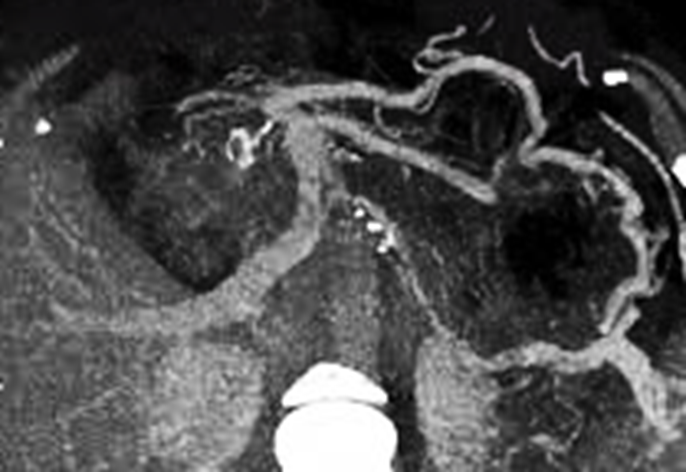

CT Imaging (Preferred Modality)

• Shows a filling defect in the splenic vein.

• Often reveals associated pancreatic pathology such as inflammation or mass.

• May demonstrate collateral veins and splenomegaly.

Featured Case Image:

The attached contrast-enhanced CT image demonstrates an occlusive thrombus in the splenic vein with surrounding pancreatic inflammation, consistent with pancreatitis-induced SVT.

What is the most likely diagnosis based on the CT findings?

A. Inferior vena cava thrombosis

B. Splenic vein thrombosis

C. Superior mesenteric artery thrombosis

D. Hepatic artery thrombosis

Explanation: The CT image reveals a filling defect in the splenic vein in the setting of pancreatitis, classic for SVT.